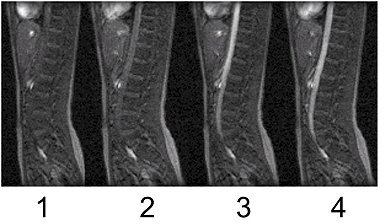

Figure 2. Optimal time to begin acquisition with Centric k-space filling

Table 1. image legend

NumberDescription

1Too soon

2Too soon

3Still too soon

4Click GO 3D.

• The first phase scan starts when the first phase delay has elapsed, counting from the time when the you clicked Go 3D. For phases 2 and up, the scan starts as soon as: the scanner is prepped, and the time elapsed since the end of the previous phase (or since you pressed the Scan button, for the first phase) is equal to or greater than the delay prescribed after the previous phase.